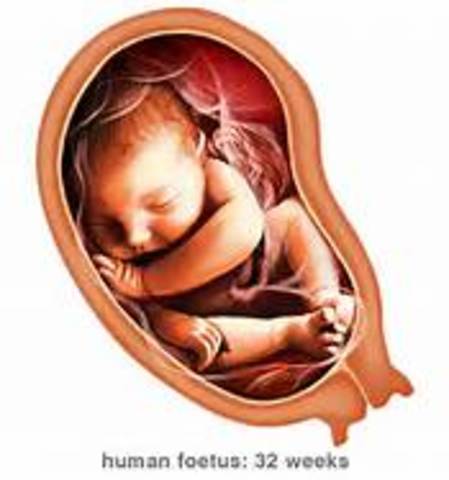

• Week 32

Week 32

During week thirty-two the baby will be asleep for most of the day. Also movement from the baby will subside because of the lack of room in the uterus.